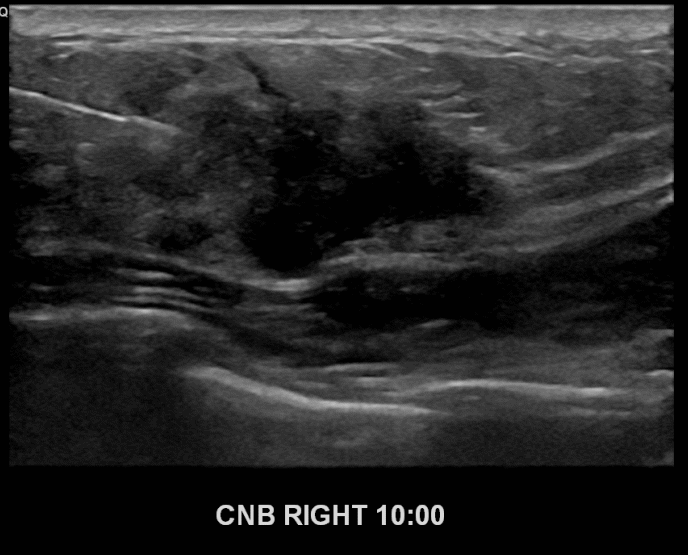

아산유외과개원후 689번째 유방암진단

상기환자 외부건진상이상소견으로 내원하신 40대여성분으로 우측유방

의심스러운 혹 조직검사시행후 유방암 진단되었습니다